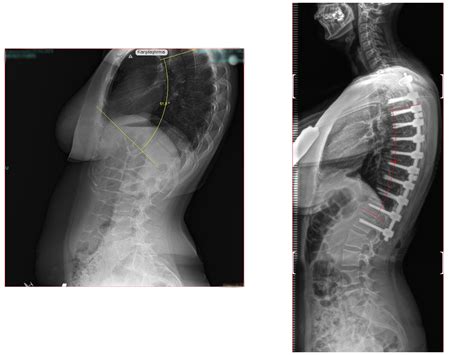

Spinal involvement in mucopolysaccharidosis IVA (Morquio-Brailsford or Morquio A